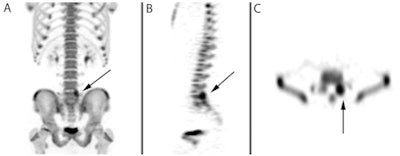

| Images are of a 14-year-old male with low back pain. Maximum intensity projection (MIP) image (A) of the lower thoracic and lumbar spine and pelvis shows increased uptake at the left pars interarticularis (arrow) that is consistent with pars stress fracture. Sagittal slice (B) and transverse slice (C) show the localization of uptake (arrow) in the pars articularis. All images courtesy of Dr. Laura Drubach. |